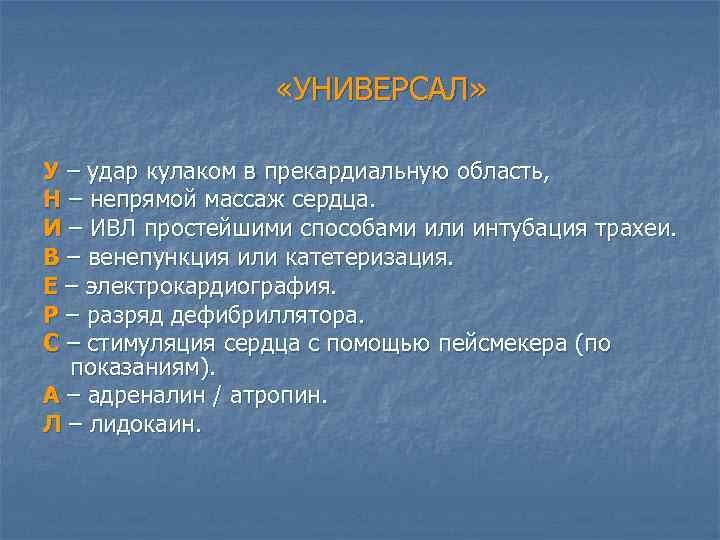

«УНИВЕРСАЛ» У – удар кулаком в прекардиальную область, Н – непрямой массаж сердца. И – ИВЛ простейшими способами или интубация трахеи. В – венепункция или катетеризация. Е – электрокардиография. Р – разряд дефибриллятора. С – стимуляция сердца с помощью пейсмекера (по показаниям). А – адреналин / атропин. Л – лидокаин.